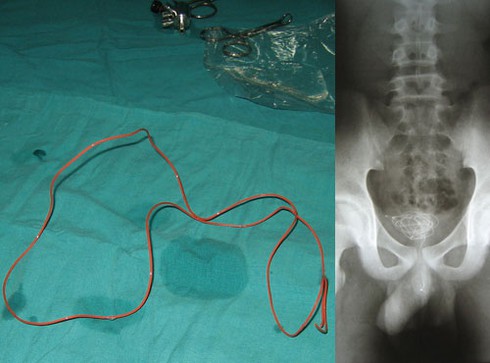

Sợi dây điện lõi đồng dài 40 cm vừa được các bác sĩ khoa Thăm dò chức năng BV Đa khoa Nghệ An lấy ra từ bụng bệnh nhân Đậu Văn Phú (SN 1979, trú TP Vinh, Nghệ An). Hiện anh Phú đã ổn định sức khỏe và vừa xuất viện.

Trước đó vào ngày 4-4, anh Phú được người nhà đưa đến bệnh viện với các triệu chứng đau bụng, buồn nôn dữ dội. Kết quả chụp X-quang, nội soi phát hiện trong ổ bụng bệnh nhân có dị vật khá dài, kéo từ môn vị tới hành tá tràng.

Sau khoảng 15-20 phút, các bác sĩ đã gắp nội soi lấy ra đoạn dây điện lõi đồng. Anh Phú thú nhận tự mình nuốt đoạn dây này vào bụng cách đây hai năm trong một lần thách đố với bạn bè.